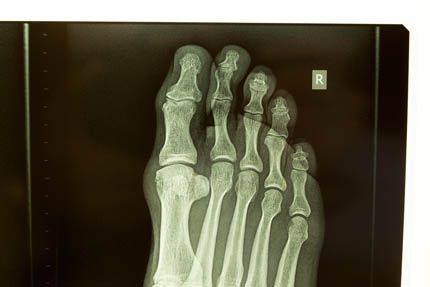

irrefutable evidence June 13, 2014injuryfucked, x-raystriker Almost a year later the foot is still sore, X-rays show “…early osteoarthritis involving the distal interphalangeal joint of the big toe and a fracture near the head of the proximal phalanx…”. Awesome.